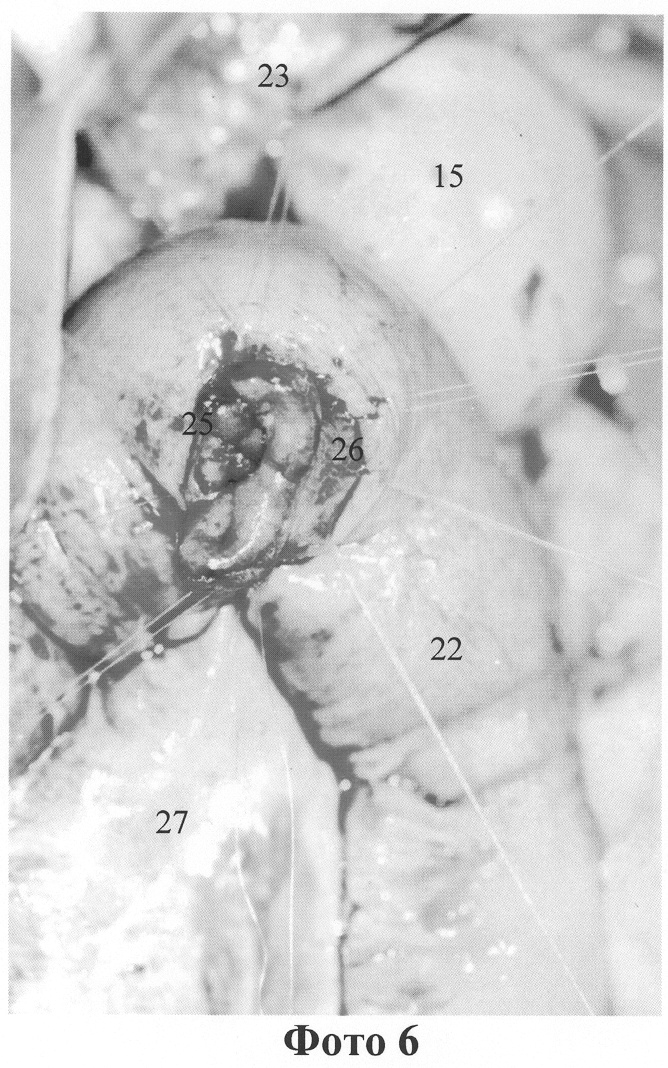

Интрадуоденальное исследование: БДС расположен на 2 см дистальнее края иссеченной кишки.

Конец отводящей петли тощей кишки проведен через окно в мезоколон в верхний этаж брюшной полости. Сформирован энтеродуоденоанастомоз однорядным серозно-мышечно-подслизистым швом мононитью. На этой же петле, на расстоянии 10 см от энтеродуоденоанастомоза, наложен конце-петлевой гастроэнтероанастомоз (приложение фото 4, 19 – культя желудка взята на держалки, растянута, 22 – петля тонкой кишки, используемая для конце-петлевого гастроэнтероанастомоза; приложение фото 5, 19 – подслизистый слой культи желудка, 24 – слизистая оболочка культи желудка, 22 – держалками фиксирована растянутая цилиндрическая трубочка культи желудка, фото 6, 15 – культя желудка, 22 – петля тонкой кишки конце-петлевого гастроэнтероанастомоза, 25 – введен назогастральный зонд в полость культи, 26 – этап наложения прециционного шва, открытая адаптация краев сшиваемых тканей (обнажен подслизистый слой культи), 27 – брыжейка тонкой кишки). Отводящая петля тощей кишки уложена параллельно ДПК, фиксирована в таком положении серо-серозными швами. Конец приводящей петли тощей кишки (на уровне дуоденоеюнального перехода) анастомозирован по типу “конец в бок” с отводящей петлей. Окно в брыжейке ободочной кишки ушито. Оментизация культи желудка и анастомозов.